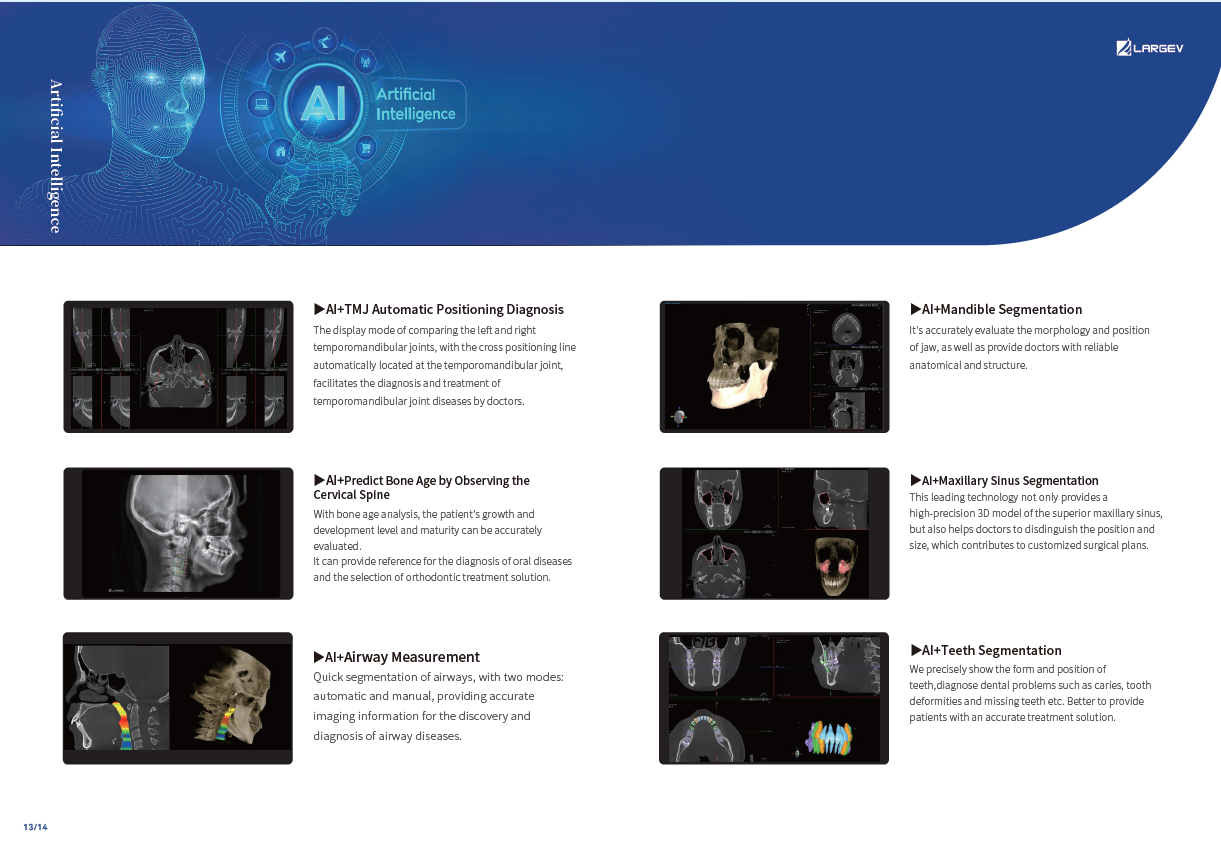

Advanced Technology and AI Features

AI + Low-Dose Dental CBCT Technology

- The integrated AI image processor enhances CT quality while reducing radiation exposure.

Consequently, each 3D scan provides superior clarity at a lower dose, ensuring patient safety.

Next, Nerve Detection with Dental CBCT (AI+Nerve)

The system automatically identifies and labels the neural tube within the CT image.

This function simplifies diagnosis and supports more precise surgical planning.

T-MAR Metal Artifact Reduction in LargeV Dental CBCT

With the new T-MAR module, the system automatically removes metal artifacts and corrects image distortions intelligently.

Hence, the final images remain clear, accurate, and clinically reliable.

Furthermore, AI+PAN Dental CBCT Imaging enhances precision.

- The system rebuilds panoramic views directly from CBCT data using AI.

- Panoramic auto-focus and multi-layer technology select the best curve automatically.

- Therefore, the final image is cleaner and easier to read.

Finally, CEPH Measurement (Optional) in Dental CBCT (AI+CEPH)

The AI model analyzes large data sets to detect orthodontic landmarks and generate accurate cephalometric measurements and reports.

Therefore, orthodontists can assess and plan treatments with confidence.